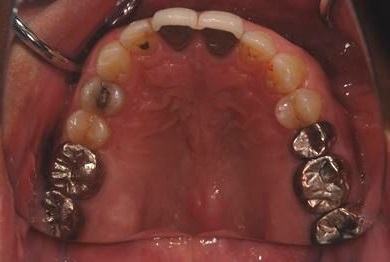

インプラントの症例写真 IMPLANT

インプラント治療

| 性別/年齢 | 男性 / 59歳 | ||||||||||||||||||||||||||||||||

| 治療方針 | 欠損部分インプラント治療により、機能的・審美的回復を行う。 | ||||||||||||||||||||||||||||||||

| 治療内容 | インプラント2本、ハイブリッドセラミック2本 | ||||||||||||||||||||||||||||||||